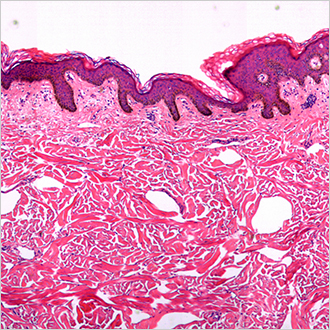

TM-Microscopy

Diese Lösung ermöglicht eine optimierte Verbreitung und den optimierten Zugang zu anatomisch-pathologischen Bildern durch die Erfassung, Speicherung und Bereitstellung von Bildern im TM-Microscopy-Viewer. Sie ermöglicht eine hohe Diagnostikqualität durch die präzisere Labordiagnostik und den verbesserten Austausch zwischen Pathologen. Weiterlesen?